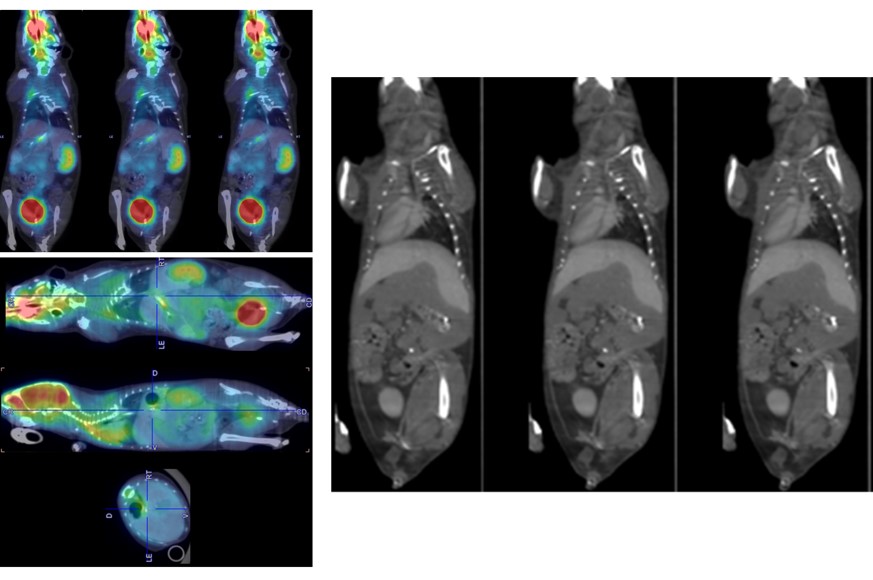

The PET/CT Si78 is a molecular imaging system for sequential Positron Emission Tomography (PET) and X-Ray Microtomography (uCT). The fully shielded scanner, the animal welfare solutions and the experimental workflows are designed to support high throughput translational preclinical research in all field s of nuclear molecular imaging research.

ParaVision 360 software offers the complete solutions from subject & study handling, to scan execution, image reconstruction co-registration & image fusion, data analysis and automatic report generation. It easily links imaging data to the most advanced quantitative PET data analysis and kinetic modelling features offered by the PMOD biomedical image quantification software of Bruker.

PET Features

• Up to 0.7 mm spatial resolution

• Up to 12 % sensitivity

• 150 x 80 mm FOV

CT Features

• 52 µm resolution

• 80 (200) x 80 mm FOV single (multiple) bed positions